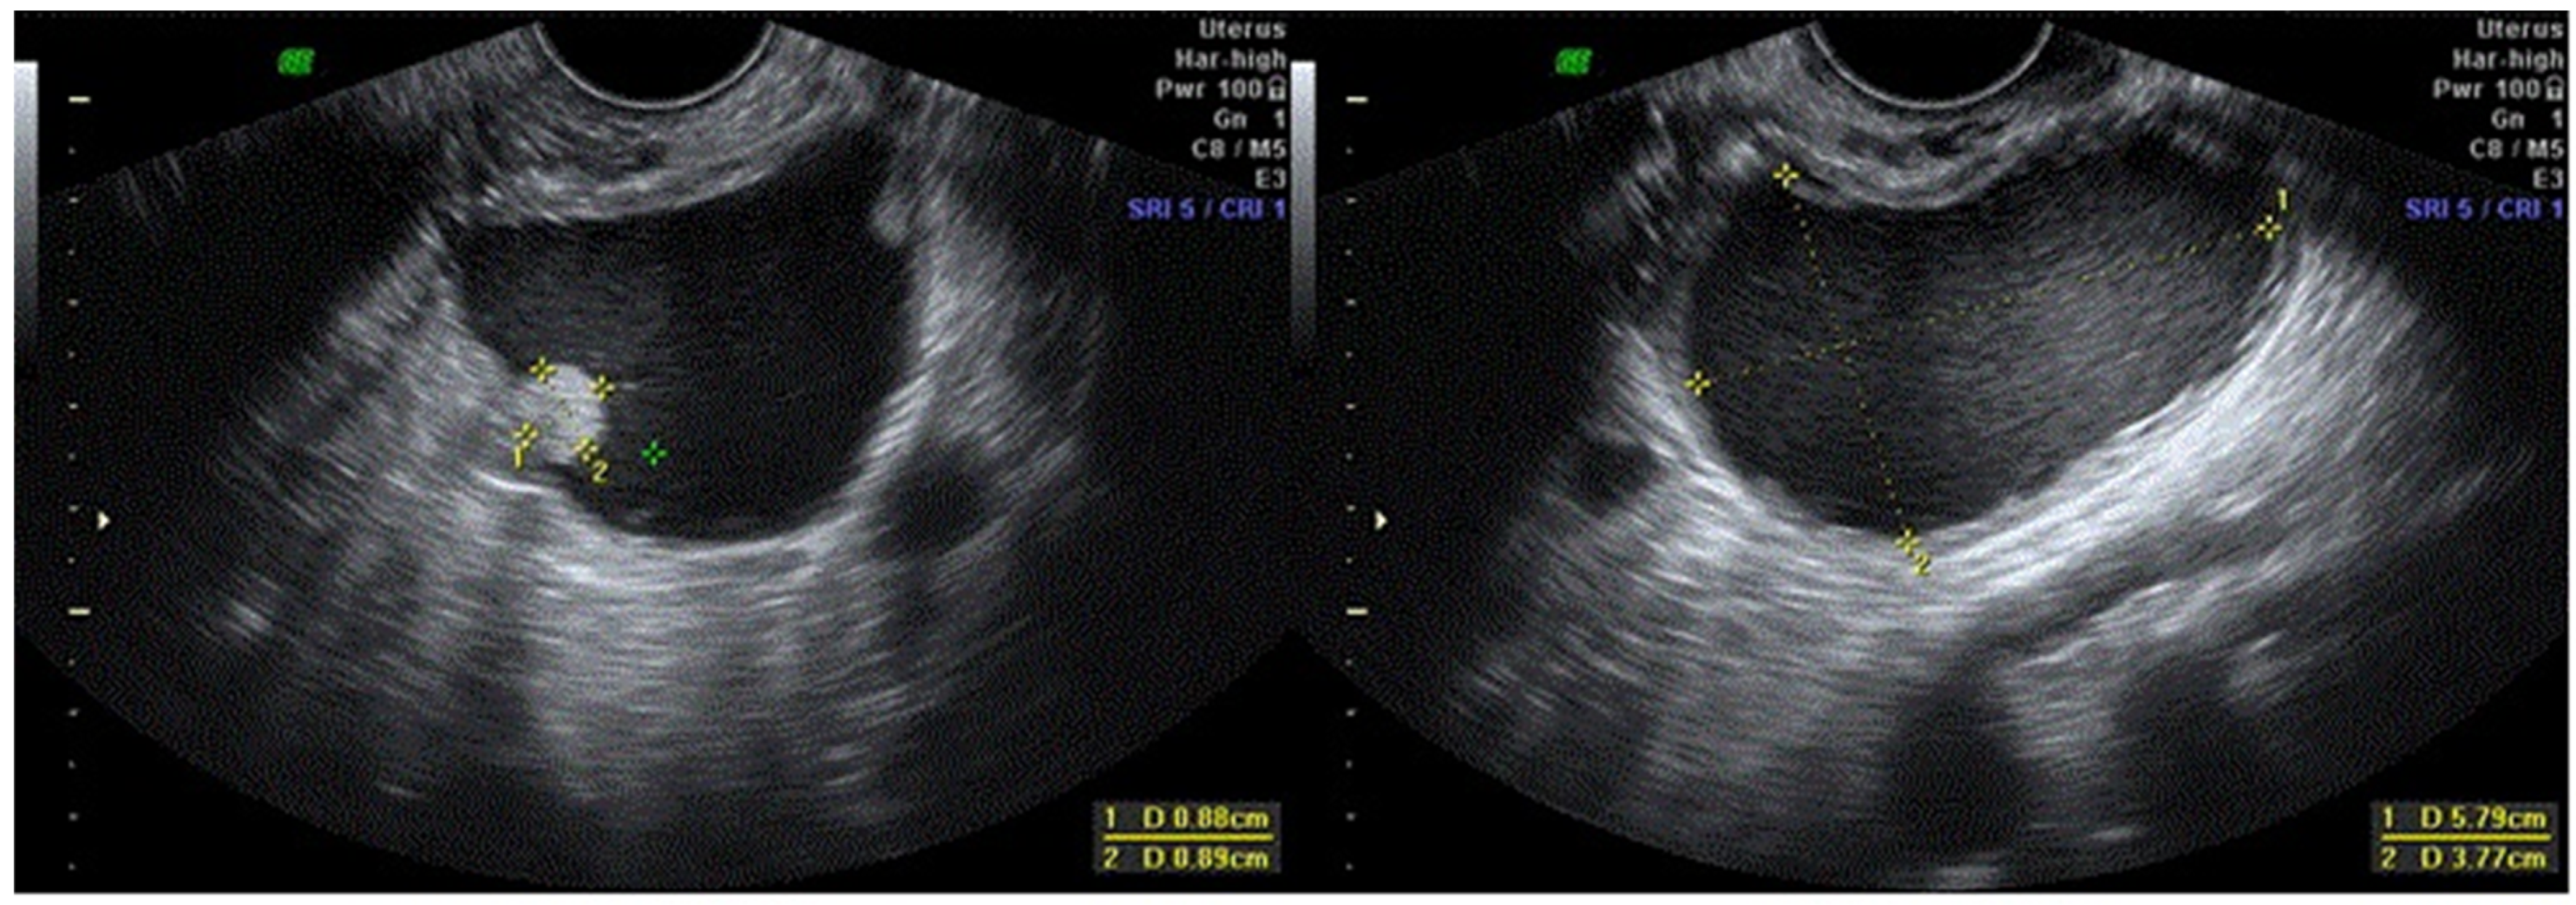

2.2. TVUS Evaluation of Adnexal Masses

- Van Holsbeke, C.; Van Calster, B.; Guerriero, S.; Savelli, L.; Paladini, D.; Lissoni, A.A.; Czekierdowski, A.; Fischerova, D.; Zhang, J.; Mestdagh, G.; et al. Endometriomas: Their ultrasound characteristics. Ultrasound Obstet. Gynecol. 2010, 35, 730–740. [Google Scholar] [CrossRef]